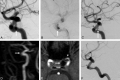

Fig 1.

A 76-year-old woman (patient 2) presents with a lobulated 4.1-mm recurrence of a previously coiled 8-mm ICA aneurysm (arrow, A). After placement of a single PED, the recurrence remains visible (arrow, B). At the 6-month angiographic follow-up, recurrence of the aneurysm neck is smaller, but still visible (arrow, C). MRA performed 13 months after PED placement demonstrates complete occlusion of the aneurysm (arrows, D–E) and patency of the parent artery (arrowhead, E). Angiography at 30 months confirms the results of the MR angiography, demonstrating complete occlusion of the aneurysm and excellent reconstruction of the parent artery (F).